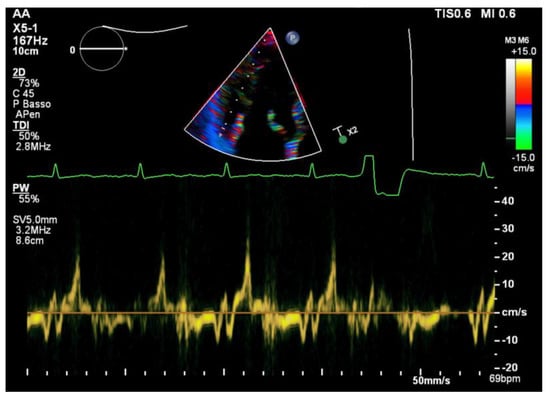

All of the patients underwent transthoracic echocardiography with ECG tracing. Echocardiography was performed using a Philips EpiQ CvX 7C echocardiograph with a Philips X5-1 3D probe. Every patient was screened with basal echocardiography, with careful morphological evaluation of the mitral valve (MV) and grading of the mitral regurgitation (MR) [13], along with a specific protocol to investigate tissue Doppler imaging of the mitral annulus, 3D imaging of the mitral valve and 3D full volume reconstruction of the ventricle. Bileaflet MVP was defined as the prolapse of both leaflets into the left atrium above the mitral annulus by at least 2 mm during the end-systole period, which is visualized in parasternal long axis view (PLAX), as shown in Figure 1 [14]. Mitral valve leaflets’ thickness and length were measured with 2D imaging in PLAX in meso-diastole, whereas the maximum height of the prolapse was measured during the end-systole period. Leaflet thickness was measured in diastole at the thickest point of the leaflet. Leaflets were defined myxomatous based on their morphology and thickness (greater than 5 mm). Antero-posterior and inter-commissural diameters of the mitral valve annulus (MVA) were measured in 2D in PLAX and in A2C views, respectively, both during the diastole and end-systole periods to investigate the presence of paradoxical systolic annular expansion [15]. Antero-posterior and inter-commissural diameters were also measured with 3D imaging, along with the MVA circumference and area. The anterior mitral leaflet (AML) length/AP diameter ratio was also calculated [13]. All of the anatomical parameters were tested at the baseline and after an adjustment for Body Surface Area (BSA). The Tissue Doppler Pulsed Wave (TDI-PW) was measured with an effort to optimize the ultrasound beam alignment with the longitudinal motion of the MVA on both the basal left ventricular segments displayed in the apical 4 chambers view (A4C), apical 2 chambers view (A2C) and apical 3 chambers view (A3C), thus providing 6 tracings for each patient. In this article, we refer to the “spiked systolic high-velocity signal” described by Muthukumar et al. as S3 [16], example shown in Figure 2. Absolute values of S1, S2 and S3 waves were measured. Mechanical dispersion was measured using the TDI, speckle tracking and Electro-Mechanical Window (EMW). The time from the onset of the R wave to the onset of the S1 wave, the end of S2/S3 wave, and the peak of S3 wave were measured using the simultaneous ECG monitoring to assess the presence of dyssynchrony by calculating the standard deviation of each time in all of the six TDI pulsed wave Doppler tracks within the same patient [17]. The speckle tracking (STE) analysis was performed on the workstation using the software CMQ 10 for Q-LAB, and global longitudinal strain (GLS) was calculated using the A4C, A2C and A3C views with a good display of the endocardial border. The endocardial border was outlined by a single operator at the end-diastolic phase of the cardiac cycle. Minor adjustments were made to optimize tracking throughout the cardiac cycle. Mechanical dispersion (MD) was calculated as the standard deviation (SD) of the times measured from the onset of R on the ECG to the peak strain (TPS) in each of the 18 segments of the left ventricle, and sub-analyses were performed separately considering the basal segments alone, the mid-ventricular segments alone, the apical segments alone and basal segments combined with middle segments as well. The transversal shift measured by CMQ 10 using Q-LAB software was analyzed as well in order to quantify the transversal motion of the ventricular walls throughout the cardiac cycle. Additionally, the GLS pattern was analyzed to research a specific double peak pattern that is suggestive of arrhythmic events and dyssynchrony.

In the TDI analyses, the S3 velocity of the inferolateral basal segment was significantly increased in the ICD-MVP population (ICD-MVP: 28.2 ± 11.7; A-MVP: 16.5 ± 11.1; p = 0.02).

Figure 2. A pulsed wave tissue Doppler signal on the basal inferolateral wall from the same patient of Figure 1 (aMVP group). Note the spiked high velocity signal (Pickelhaube sign).